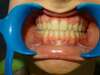

Intrabuccale face - Avant traitement 1 (03-03-2018) - 1 2

Intrabuccale face - Fin de traitement (15-01-2024) - 53 1